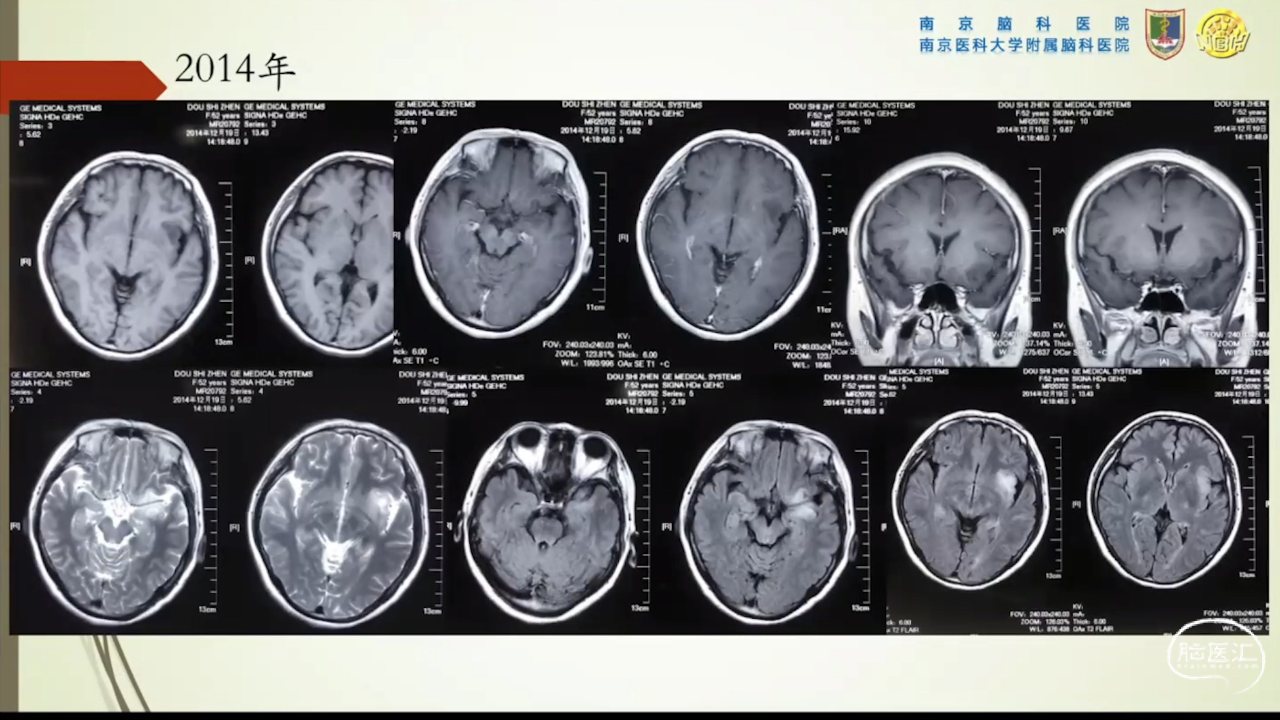

胶质瘤是发病率最高的颅内肿瘤(约占44.69%),岛叶是神经胶质瘤的好发部位,大约有25%的低级别胶质瘤及10%的高级别胶质瘤发生在岛叶,大多数岛叶胶质瘤为低级别胶质瘤。岛叶在调节内脏感觉运动、控制心血管交感活性、传入躯体感觉中均起重要作用。它也参与了痛觉的传递、运动规划、自主性吞咽、味觉、听觉、前庭功能、情绪、认知能力和语言能力。因为岛叶解剖结构复杂,并覆盖有高级语言皮层、白质束及重要的血管结构,故岛叶部位的手术难度极大。

讲题岛叶胶质瘤的显微手术治疗